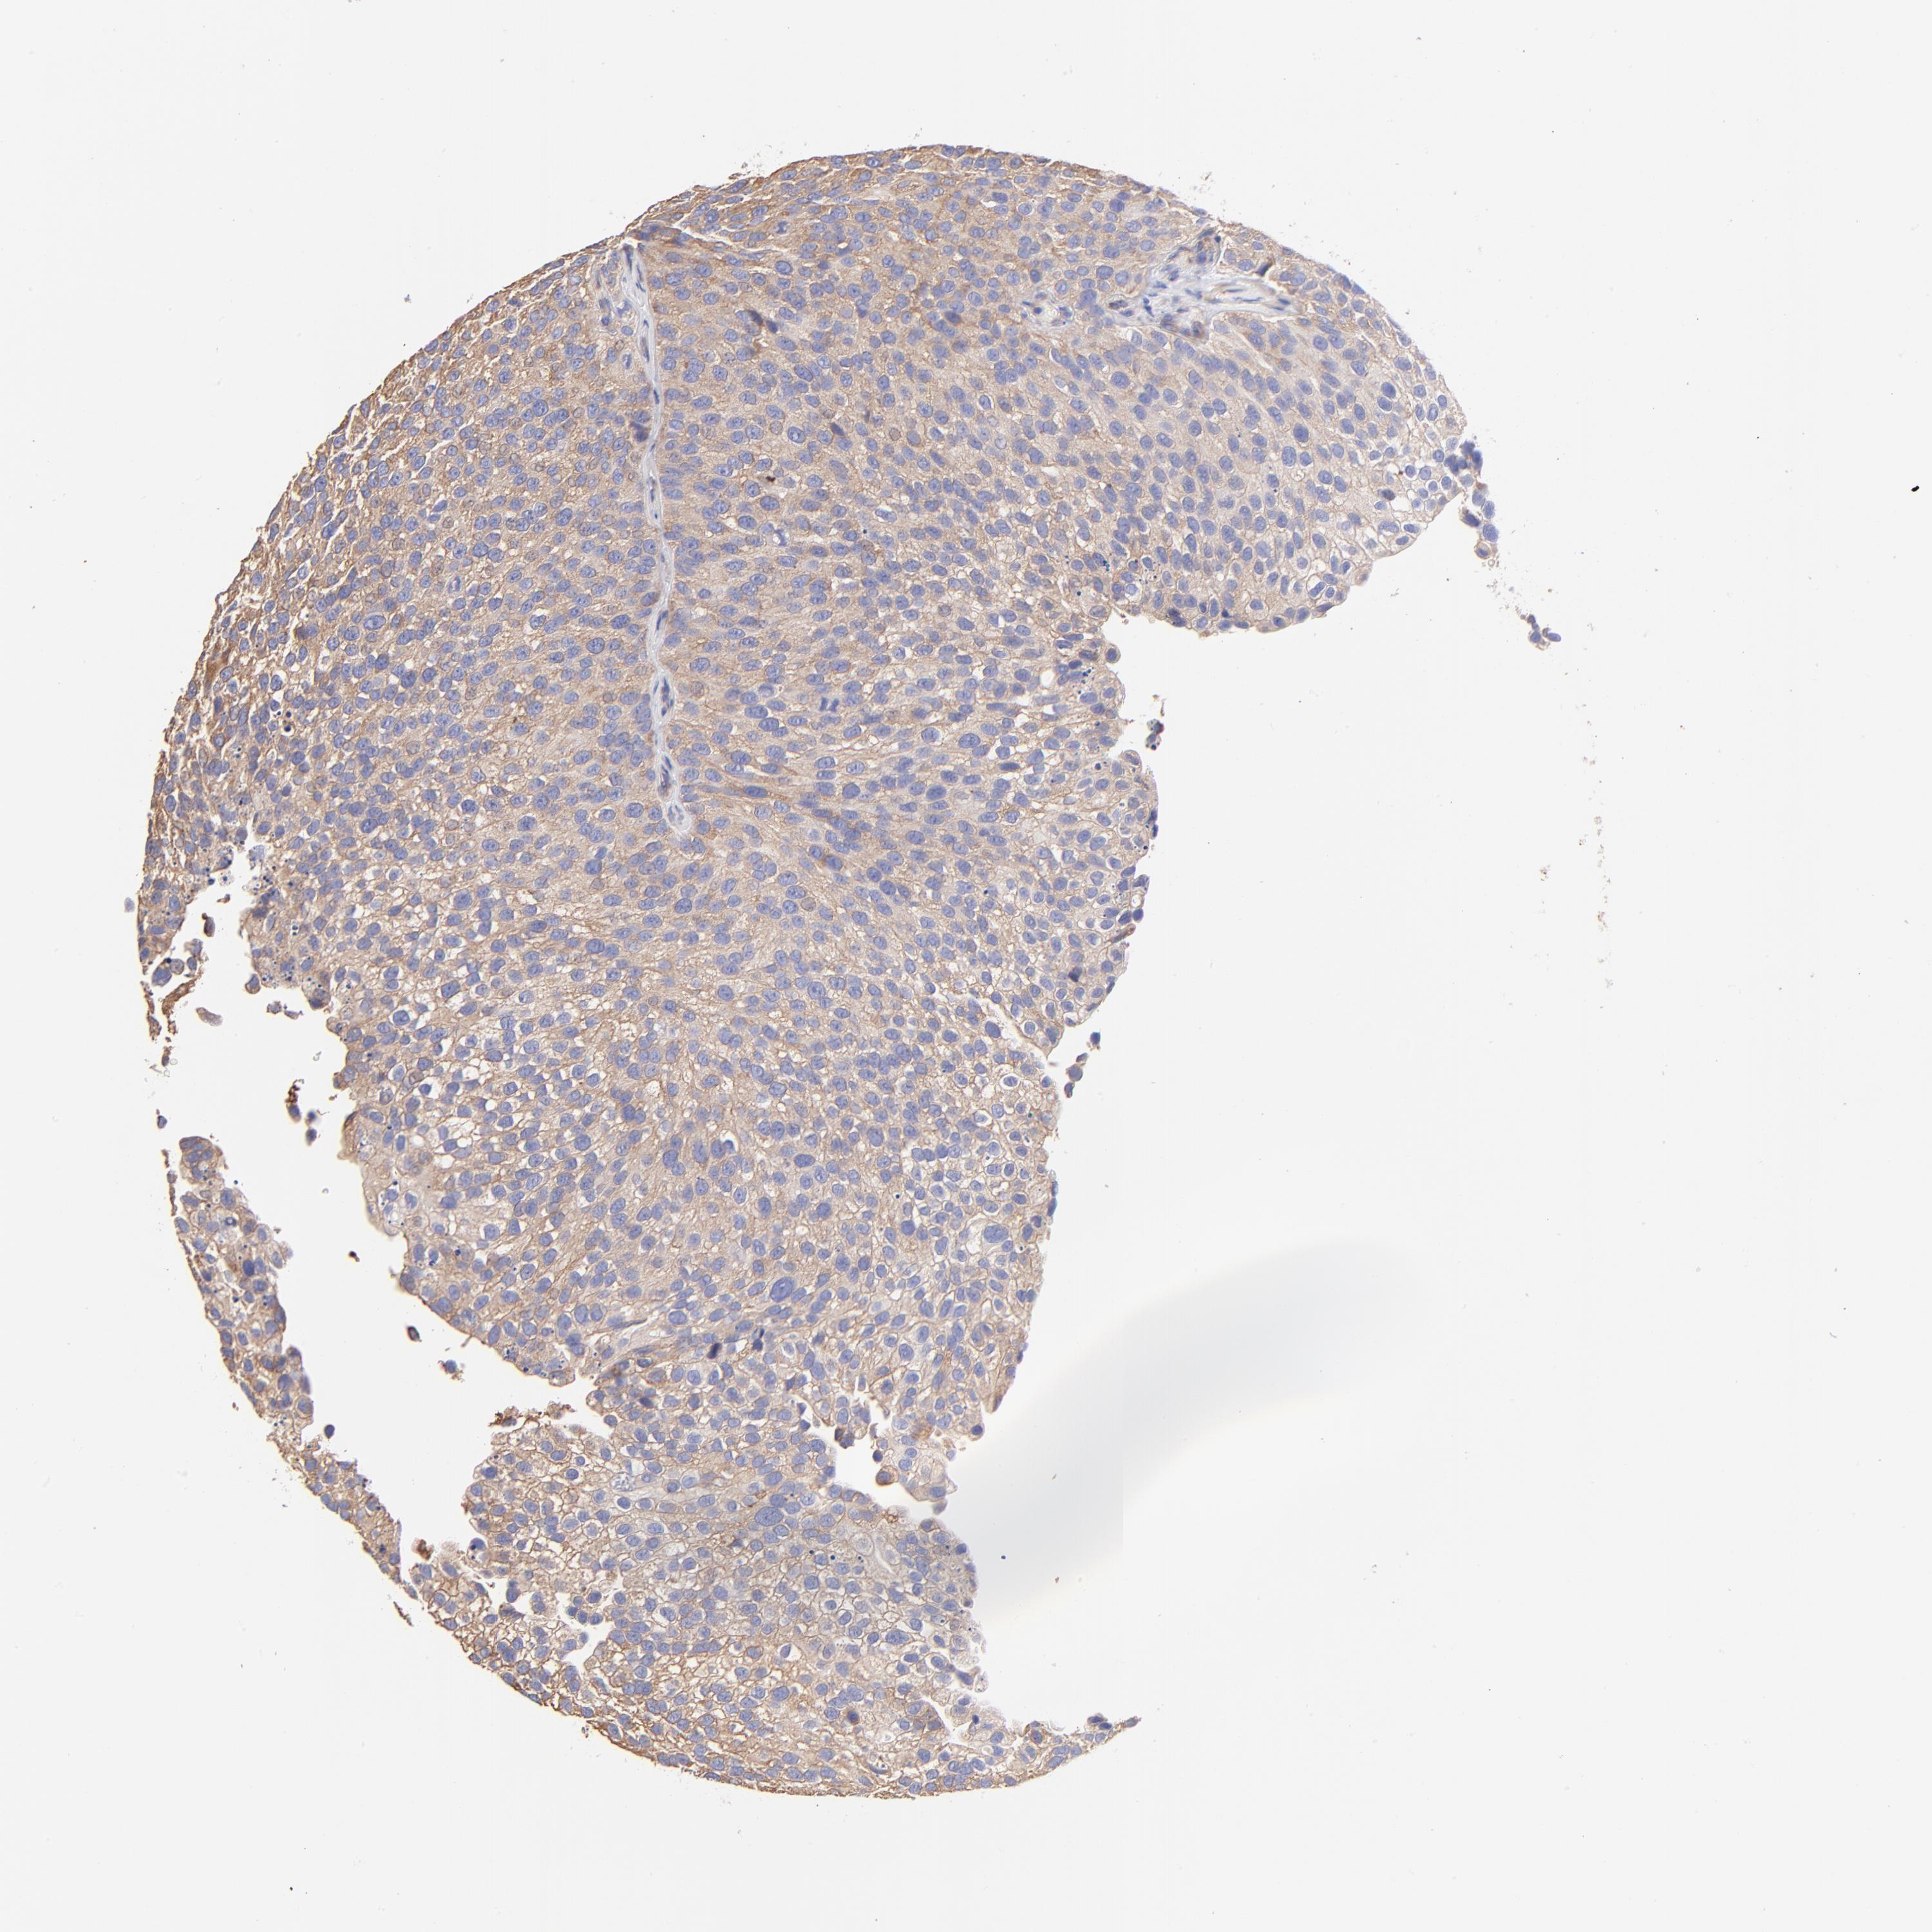

UROTHELIAL CANCER - Protein expressioni

A mouse-over function shows sample information and annotation data. Click on an image to view it in a full screen mode. Samples can be filtered based on level of antibody staining by selecting one or several of the following categories: high, medium, low and not detected. The assay and annotation is described here.

Note that samples used for immunohistochemistry by the Human Protein Atlas do not correspond to samples in the TCGA dataset.

Antibody stainingi

Antibody staining in the annotated cell types in the current human tissue is reported as not detected, low, medium, or high, based on conventional immunohistochemistry profiling in selected tissues. This score is based on the combination of the staining intensity and fraction of stained cells.

Each image is clickable and will lead to virtual microscopy that enables deeper exploration of all samples and also displays staining intensity scores, fraction scores and subcellular localization as well as patient and tissue information for each sample.

Antibody HPA002651

Staining

High

Medium

Low

Not detected

Intensity

Strong

Moderate

Weak

Negative

Quantity

>75%

75%-25%

<25%

None

Location

Nuclear

Cytoplasmic/membranous

Cytoplasmic/membranous,nuclear

Urothelial carcinoma, High grade

Urothelial carcinoma, Low grade